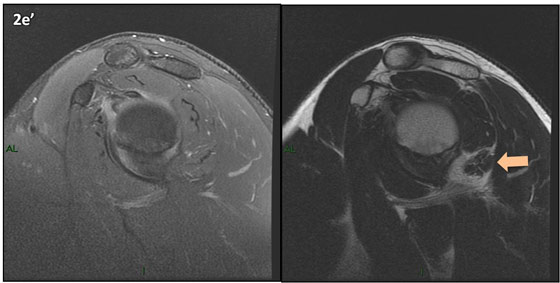

Figura 2 (a-j)': Imagens consecutivas de RM no plano sagital nas ponderaçõesT2 com supressão de gordura (DP SG) à esquerda e T2 à direita. Clique na seta para passar as imagens.

Figuras 2b a 2j’: Acompanhando o tendão do redondo menor (seta amarela fina) é possível notar lipossubstituição ao redor da junção miotendínea (setas amarelas grossas) e a atrofia principalmente da porção mais lateral (seta salmão). A porção mais medial (seta branca) tem volume preservado.

Repare que estas alterações também não são evidentes nas imagens com supressão de gordura no plano sagital.